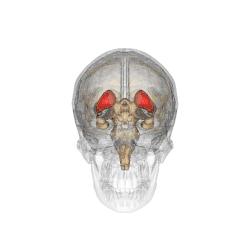

![]() Caudate nucleus (in red) shown within the brain | |